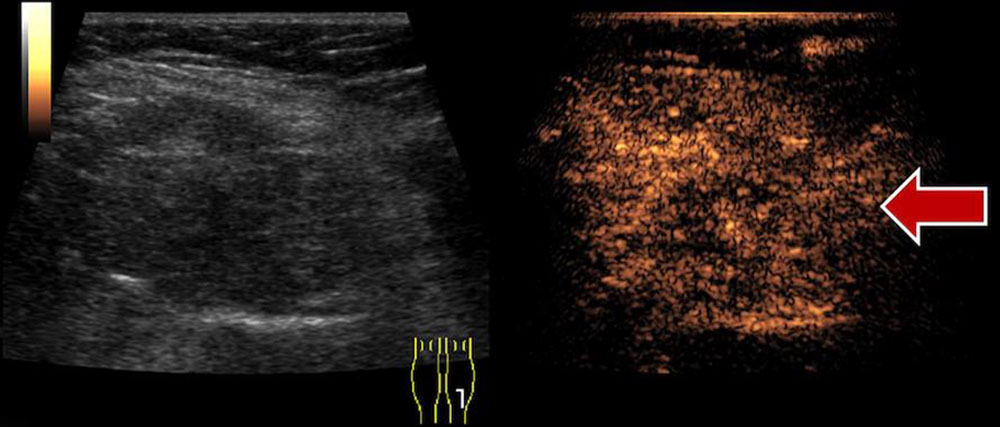

Ultrasound elastography allows for imaging of the hardness / softness of a tissue in color.

ElastographyColor-coded imaging of tissue hardness/softnessDifferentiation of therapy-induced effects, differential diagnosis